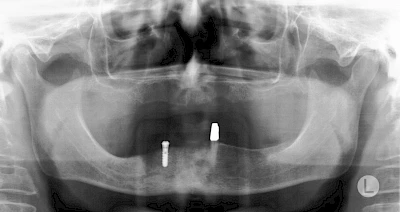

Damit Implantate an der richtigen Stelle im Kieferknochen platziert werden könen, gibt es heute vielfältige Möglichkeiten der Planung. In vielen Situationen kann die Erfahrung des Zahnarztes ausreichend sein.

Nicht selten ist jedoch auch eine technisch aufwändigere Vermessung im Vorfeld sinnvoll, z. B.:

- Wenn sich der Kieferknochen abgebaut hat

- Wenn der Nervverlauf im Unterkiefer beachtet werden muss

- Wenn die Ausdehung der Kieferhöhle im Oberkiefer beachtet werden muss

- Wenn wenige Restzähne keine gute Orientierung erlauben

In diesen Fällen kann die Planung mittels verschieden aufwendiger Röntgen-Techniken (Übersichtsaufnahme, DVT) ggf. unter Zuhilfenahme speziell angefertigter Planungsschablonen sinnvoll sein.